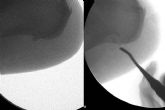

Para ello, los podólogos en Donostia de Clínica del Pie Ariño guiados en todo momento por un ecógrafo de alta definición realizan una liberación parcial de la fascia plantar y eliminación del espolón calcáneo, con una incisión de 2 mm, sin necesidad de poner puntos. Después de la intervención, el paciente sale caminando del quirófano por su propio pie, con un vendaje y calzado especial, sin necesidad de muletas ni bastones. Es un procedimiento ambulatorio que asegura una recuperación rápida.

A diferencia de la cirugía convencional, en la cirugía ecoguiada se utiliza anestesia local, la recuperación postquirúrgica es muy rápida, el sangrado y el dolor es mínimo, no se ponen puntos ni isquemia, la cicatrización es muy rápida, reduciendo el riesgo de infección y problemas circulatorios. Se trata de una intervención rápida y sencilla que dura 45 minutos aproximadamente. Es una técnica indicada cuando los tratamientos conservadores no hayan funcionado y el paciente lleve más de 6 meses con molestias. Es muy importante realizar un buen diagnóstico previo, ya que en ocasiones acuden a consulta fascitis plantares mal diagnosticadas, con síntomas parecidos a la fascitis plantares, pero que no son y es necesario acudir a un especialista que realice un diagnóstico diferencial mediante el uso de la ecografía, radiografías o resonancia magnética nuclear.